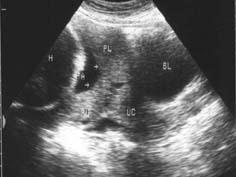

问题 患者女25岁,停经37周,阴道不规则出血来院就诊,B超检查声像图如图所示应诊断为 ( )

选项 A、先兆早产 B、以上都不是 C、前置胎盘 D、副胎盘 E、胎盘早剥

答案 C